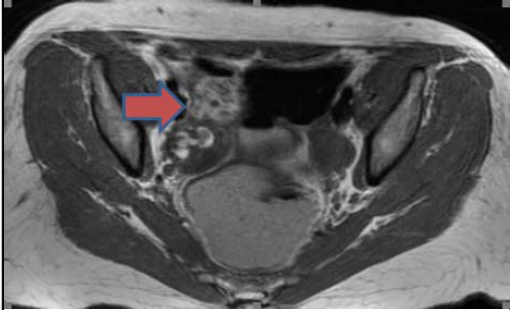

患者血清抗NMDA受体抗体回报阳性。且患者的盆腔超声及MRI提示右侧卵巢肿块,与囊性畸胎瘤表现一致。这些发现确认了抗NMDA受体脑炎的诊断。

图2 盆腔MRI发现右侧卵巢肿物,符合囊性畸胎瘤表现